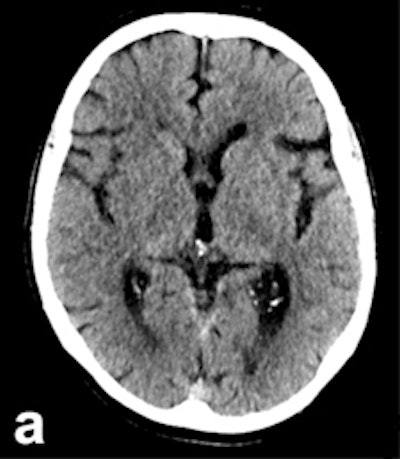

In large clinical studies, thrombectomy has been used mainly in patients whose CTs show a lower degree of severity, normally assessed using the Alberta Stroke Program Early CT Score (ASPECTS). In most of the successful studies, including ESCAPE, SWIFT PRIME, and REVASCAT, the ASPECTS must be no worse than six or seven points out of 10.

ASPECTS scoring is standard in patients who undergo CT for a recent stroke. "Doing the scores manually requires a high degree of experience, and is prone to error," Herweh said, adding that this problem can be solved by using software to calculate the scores. "It's more objective, and may be better than radiologists at evaluating patients' prognoses."

The Brainomix eASPECTS software, which has been around for some time now, is increasingly proving its value in clinical studies.

An initial validation study of 34 patients by the Heidelberg group showed that software evaluation of CT images was better than assessments by radiologists with limited training, and performed to the same level as experts. Furthermore, a U.K. study of 132 patients showed the software was at least equal to neuroradiologists, he explained.

It works from a technical viewpoint, but the key clinical question is whether this method is better than, or as good as, experts at predicting which patients have a poor prognosis. Therefore, Herweh and his colleagues carried out a third study of 212 recent stroke patients, using three experts and the software to calculate the ASPECTS retrospectively. The result was then correlated with the patients' actual clinical progress.

"What we've shown is that the software reliably predicts a poor prognosis following thrombectomy," he stated.

A low eASPECTS has a statistically significant correlation to such a prognosis. Among experts, however, this correlation was statistically significant in only one out of three cases. In other words, software-based scoring could be more objective and clinically conclusive than manual scoring by experts.